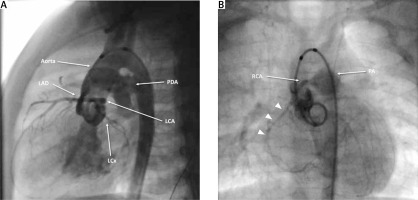

At the age of 5 months, he was admitted to our center for a PDA assessment. On physical examination, a continuous murmur was found. A chest X-ray revealed cardiomegaly. The electrocardiogram showed a normal sinus rhythm with signs of left ventricular hypertrophy. TTE established the diagnosis of PDA (4 mm) with left-to-right shunt, small PFO, and mild left ventricular dilation with preserved systolic function. The patient had cardiac catheterization for PDA assessment, which revealed an unexpected finding: an apparent ARCAPA originating from the pulmonary artery and a PDA measuring 4 × 4 mm (Figures 1 A, B). Moreover, computed tomography confirmed and showed the right coronary artery (RCA) arising from the right anterior sinus of pulmonary artery, bovine aortic arch, and a PDA of 3.5 mm in diameter and 2 mm in length (Figures 2 A, B).

Figure 1

A – Lateral view of angiogram demonstrates filling of the left coronary artery and no filling of the right coronary artery (RCA). The patent ductus arteriosus (PDA) can also be seen. B – Posterior-anterior angiogram showing RCA arising from the right anterior aspect of the main pulmonary artery with the usual course through the right atrioventricular groove (arrowheads)

LCA – left main coronary artery, PA – pulmonary artery, LAD – left anterior descending artery, LCx – left circumflex artery.